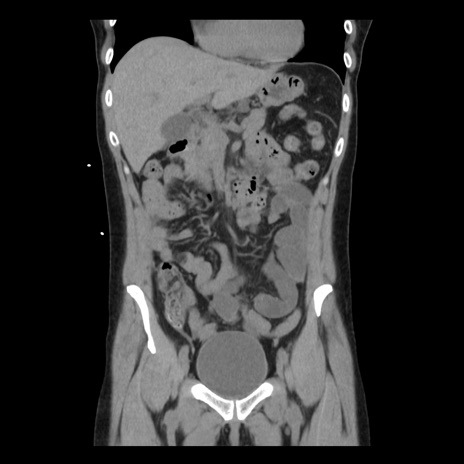

横断像

矢状断像

【症例】 50歳代女性

【主訴】 腹痛

【現病歴】前日生レバーを食べた。今朝に排便あり。 昼前に突然発症の腹痛を生じ、当院救急外来を受診した。

【既往歴】 子宮筋腫にてで子宮全摘後

【身体所見】 意識清明、腹部:平坦、軟、下腹部やや左を中心に圧痛・反跳痛あり、筋性防御あり

【データ】WBC 7800、CRP 0.07